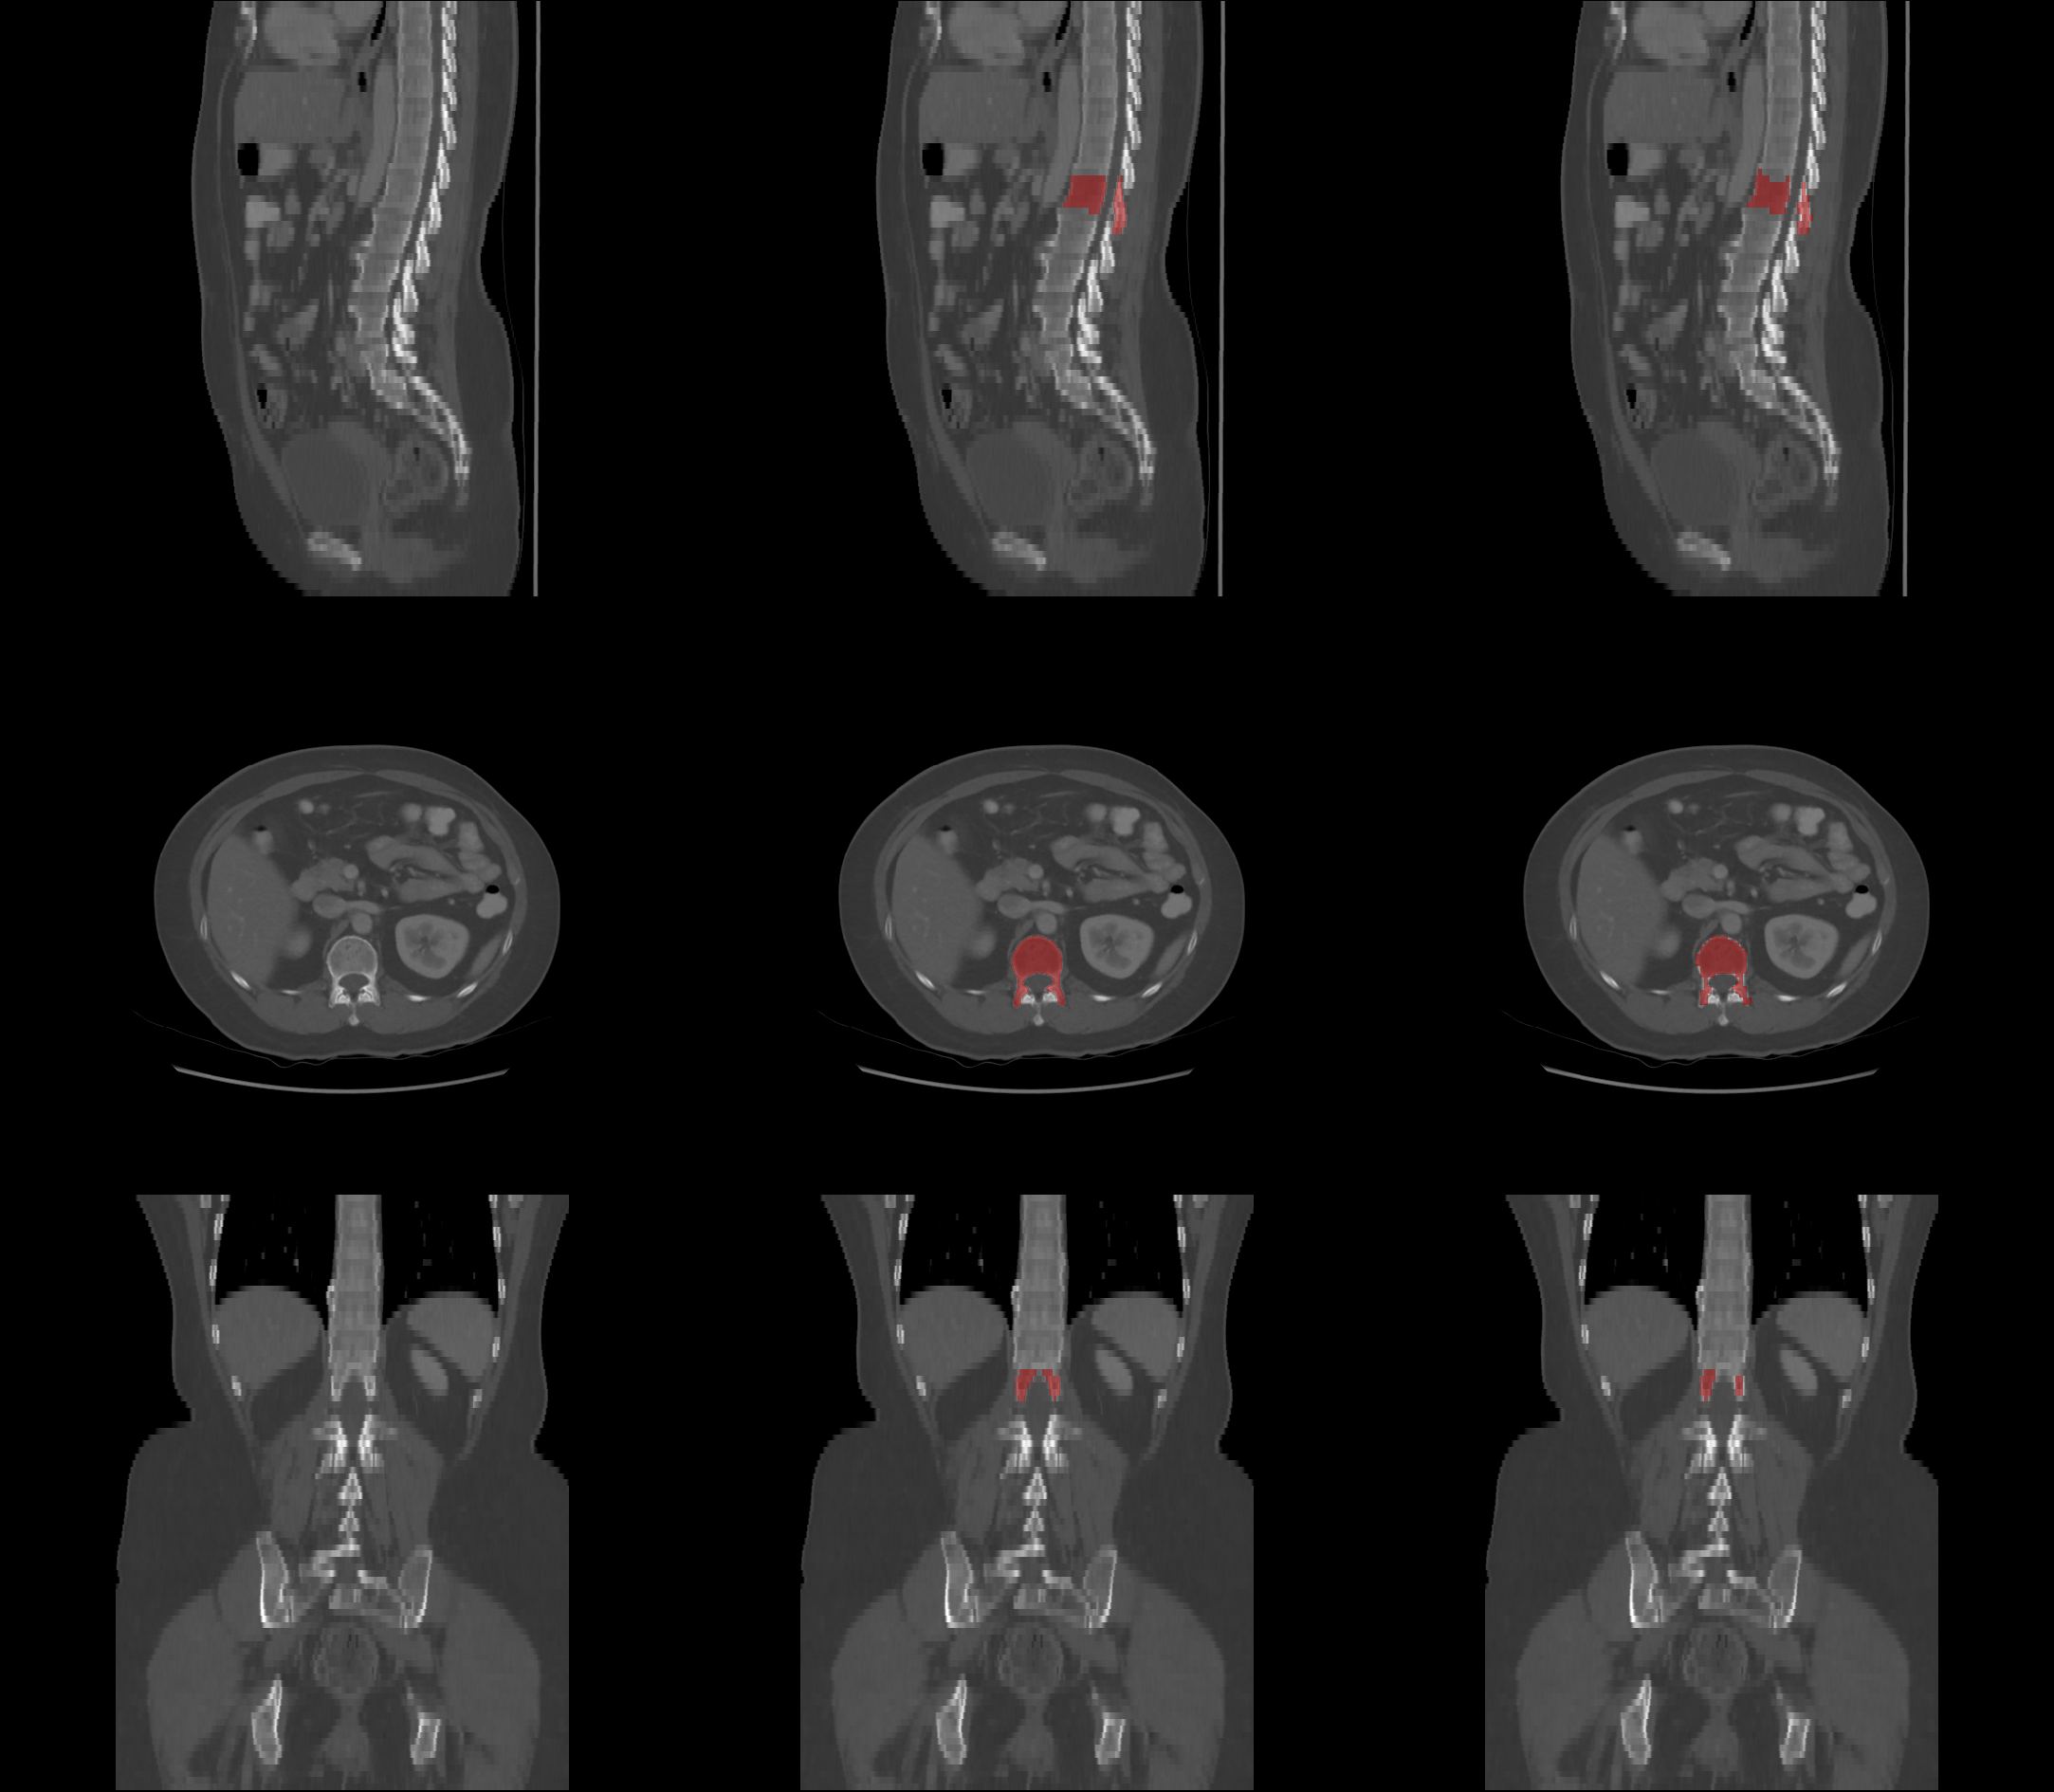

Refer to caption

Figure 1: Visualization of segmentation results on CT images. The first column shows the original images. The second column represents the segmentation results from CTSpine1K [19]. The third column displays the segmentation results from TotalSegmentator [20]. Rows correspond to different anatomical planes: the sagittal plane (S) in the first row, the axial plane (A) in the second row, and the coronal plane (C) in the third row. The region highlighted in red corresponds to the L5 vertebra, which plays a crucial role in diagnosing conditions like osteoporosis.